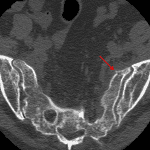

- Acute minimally displaced fracture of the left sacral ala

- Sacral fracture

Acute minimally displaced fracture of the left sacral ala.